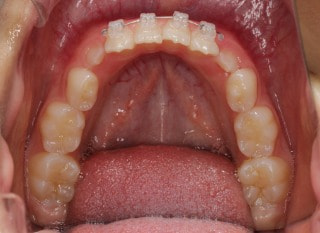

治療法:上顎急速拡大装置+クリアスナップ+フェイスマスク+上顎右側3番は開窓萌出誘導

(難症例のため、小児期の矯正を2段階にわけました)

治療前